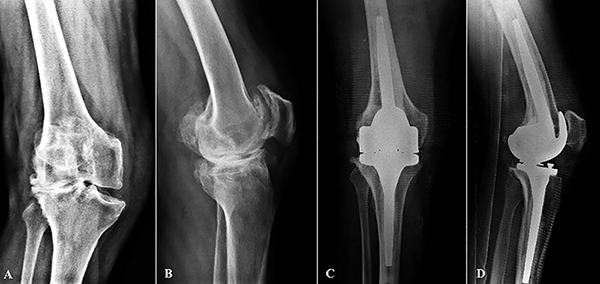

Figura 2: Caso 16. A y B) Paciente de setenta y dos años con un espaciador de cemento en rodilla derecha secundario a una infección protésica previa. C y D) Radiografías de frente y perfil a los tres años de seguimiento de prótesis abisagrada de rodilla Endo-Model.

Figura 3: Caso 22. Artroplastia de rodilla derecha a los veintitrés años de seguimiento. A y B) Radiografías frente y perfil donde se observan signos de aflojamiento y de incompetencia del ligamento colateral medial en la radiografía con estrés. C y D) Control radiográfico frente y perfil de implante protésico abisagrado a los veintidós meses de seguimiento.